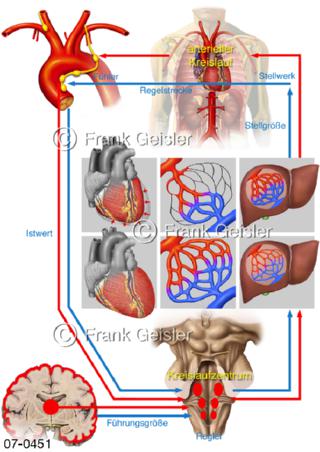

Bildergalerie Herz, Blutkreislauf

Bilder zu Herz, ein muskuläres Hohlorgan, das den menschlichen Körper durch rhythmische Kontraktionen mit Blut versorgt und dadurch die Durchblutung der Organe sichert, das Kreislaufsystem zeigt den Transport von arteriellem sowie venösem Blut durch das kardiovaskuläre System (Herz-Kreislauf-System), bestehend aus Blutgefäßen, Lymphgefäßen und dem Herz